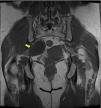

MétodosRealizamos un análisis retrospectivo de 19 casos de tumores neurogénicos de la región sacra diagnosticados y operados en nuestro centro, de los cuales ocho eran hombres y 11 mujeres, registrando una edad media al diagnóstico de 51 años (con un rango de edades entre 25 y 78 años). Seis se encontraban asintomáticos y fueron diagnosticados incidentalmente, mientras que la mayoría (11 pacientes) presentaban dolor lumbar acompañado de otros síntomas: dolor irradiado a miembros inferiores (MMII), dolor pélvico, alteraciones sensitivas y pérdida de fuerza en MMII. Dos pacientes presentaban otro síntoma principal al diagnóstico: dolor pélvico y en miembro inferior izquierdo (MII). A todos los pacientes se les realizó como mínimo una prueba de imagen (RM/TC). Nueve pacientes tenían tumores limitados al sacro o con extensión posterior, practicándose una intervención por vía posterior. En seis se realizó un abordaje exclusivamente por vía anterior debido a la localización presacra de la tumoración; y en cuatro de ellos fue preciso un abordaje tanto anterior como posterior.

MethodsWe conducted a retrospective analysis of 19 cases of patients with neurogenic tumors in the sacral area who were diagnosed and underwent surgery at our center. Of them, 8 were male and 11 were female. They had a mean age at diagnosis of 51 years (with an age range of 25-78 years). Six patients were asymptomatic and were diagnosed incidentally, while the majority (11 patients) presented with lumbar pain accompanied by other symptoms: pain radiating to the legs, pelvic pain, sensory alterations and loss of strength in the legs. Two patients presented with another primary symptom on diagnosis: pain in the pelvic region and in the left leg. All patients underwent a least one imaging test (MRI/CT scan). Nine patients had tumors limited to the sacrum or with subsequent spread, with surgery via the posterior route. In 6 cases, an exclusively anterior approach was employed owing to the pre-sacral location of the tumor; 4 cases required both an anterior and posterior approach.